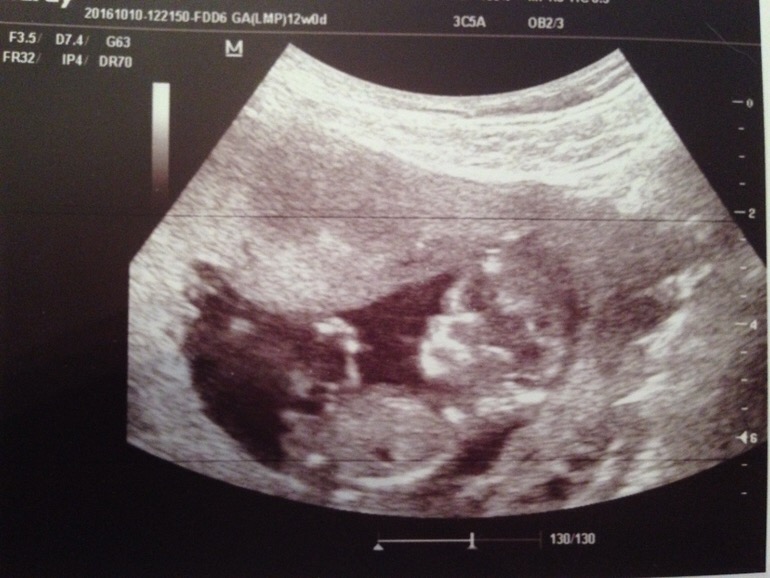

А вот и нет, на таком сроке в профиль, но в другом срезе.

Вот так смотрят бугорок на 1 скрининге .